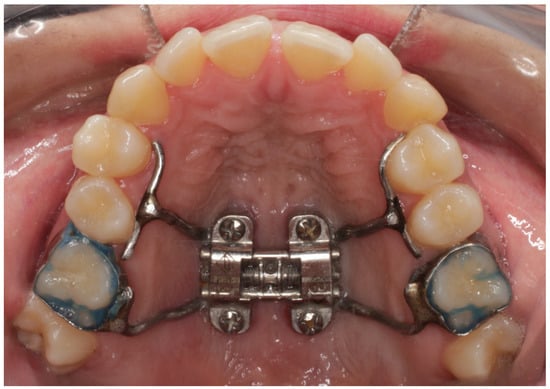

2. Materials and Methods

2.2. Procedure and Measurements